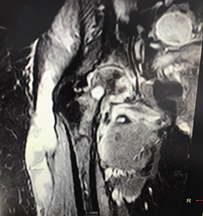

The patient reports pain in the right hip that began in May 2017, with an evolution of approximately 10 months, with functional limitation that progressively increased until she first felt the need to use a cane to walk until she was unable to walk. Therefore, on an outpatient basis, a magnetic resonance imaging (MRI) of the affected joint was requested (Figure 1); the report of said study indicates septic arthritis of the hip as the first possibility. However, due to the insidious evolution of the disease, the diagnosis is questioned and the patient is admitted through the outpatient clinic of the rheumatology service to complete studies.

Figure 1 Magnetic resonance imaging of the right hip showing bone edema, morphological alteration of the right femoral head, large amount of peripheral fluid (hyperintense) that affects the pectineus, hamstring and obturator muscles, extending through the tensor facia lata caudally for 16 cm. Collection suggestive of an inflammatory process (indicated by a red arrow). Source: MRI of the patient's right hip.